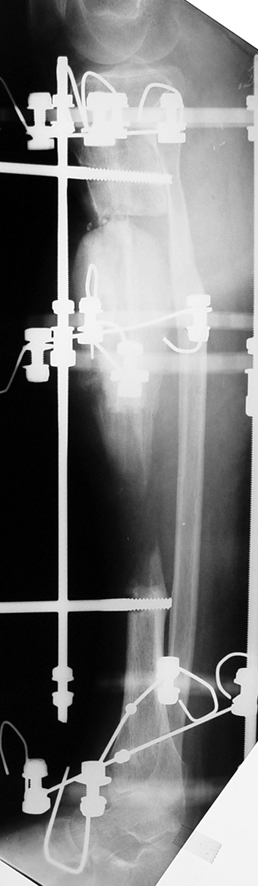

Vaka 1